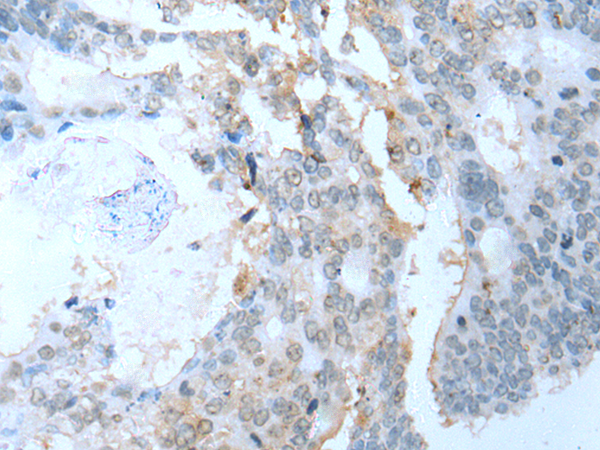

分类: 科研抗体货号: P05270别名: SSP1; SUSP1应用: WB,IHC反应种属: Human